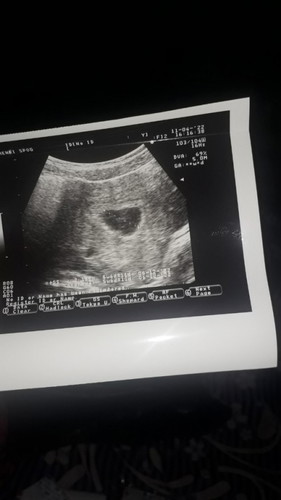

Hai bunda mau tanya nih aku tadi habis usg sedikit bingung,, Usia kandungan ku 30W 2D nah bbj nya 1550 gr Kata bidan nya itu kecil dan kurang disuruh makan es cream tiap hari,, Trus aku buka apk ini disini tertulis bbj 1300 gr dan banyak postingan bunda" yang bbj nya 1,5 gram itu normal diusia kandungan segitu dan saya udah brosing" katanya juga normal,, Jadi yang betul normal atau kurang yaa bun#seriusnanya

Bun mau tanya kenapa yaa uk di usg sama uk dihitung dari hpht kok beda,, Sedikit cerita jadi gini bun selama 3 hari aku keluar darah kayak orang haid tapi gk ada keluhan sama sekali udah priksa ke bidan dan disuruh usg ke dokter spesalis kandungan tapi pas usg katanya belum ada janinya🥺dari hitungan hpht usia kandungan ku 9 w 1d tapi diusg usianya 5w 1d mungkin ada yang sama an,,#bantusharing aku sedikit agak cemas bun karna cuma dua kemungkinan kalau gk hamil kosong ya janin tidak berkembang🥺